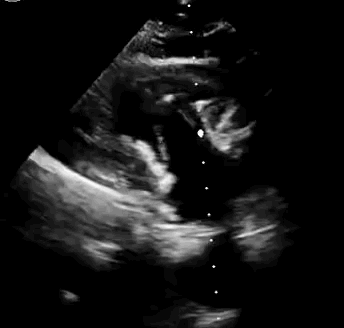

本次临床前研究经右侧颈静脉置入LuX-Valve Plus输送系统可调弯鞘管,在DSA及超声引导下将人工三尖瓣瓣膜植入到原有三尖瓣位置,利用独特的锚定技术将人工瓣膜支架可靠固定在预定的位置。